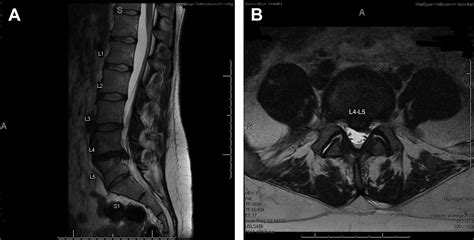

Diagnosing partial sacralization of L5 typically involves a combination of physical examination and imaging tests. Common diagnostic methods include:

• CT scans: For detailed images of the spine, including the extent of the fusion.

• MRI scans: To assess soft tissue structures and identify any nerve compression.